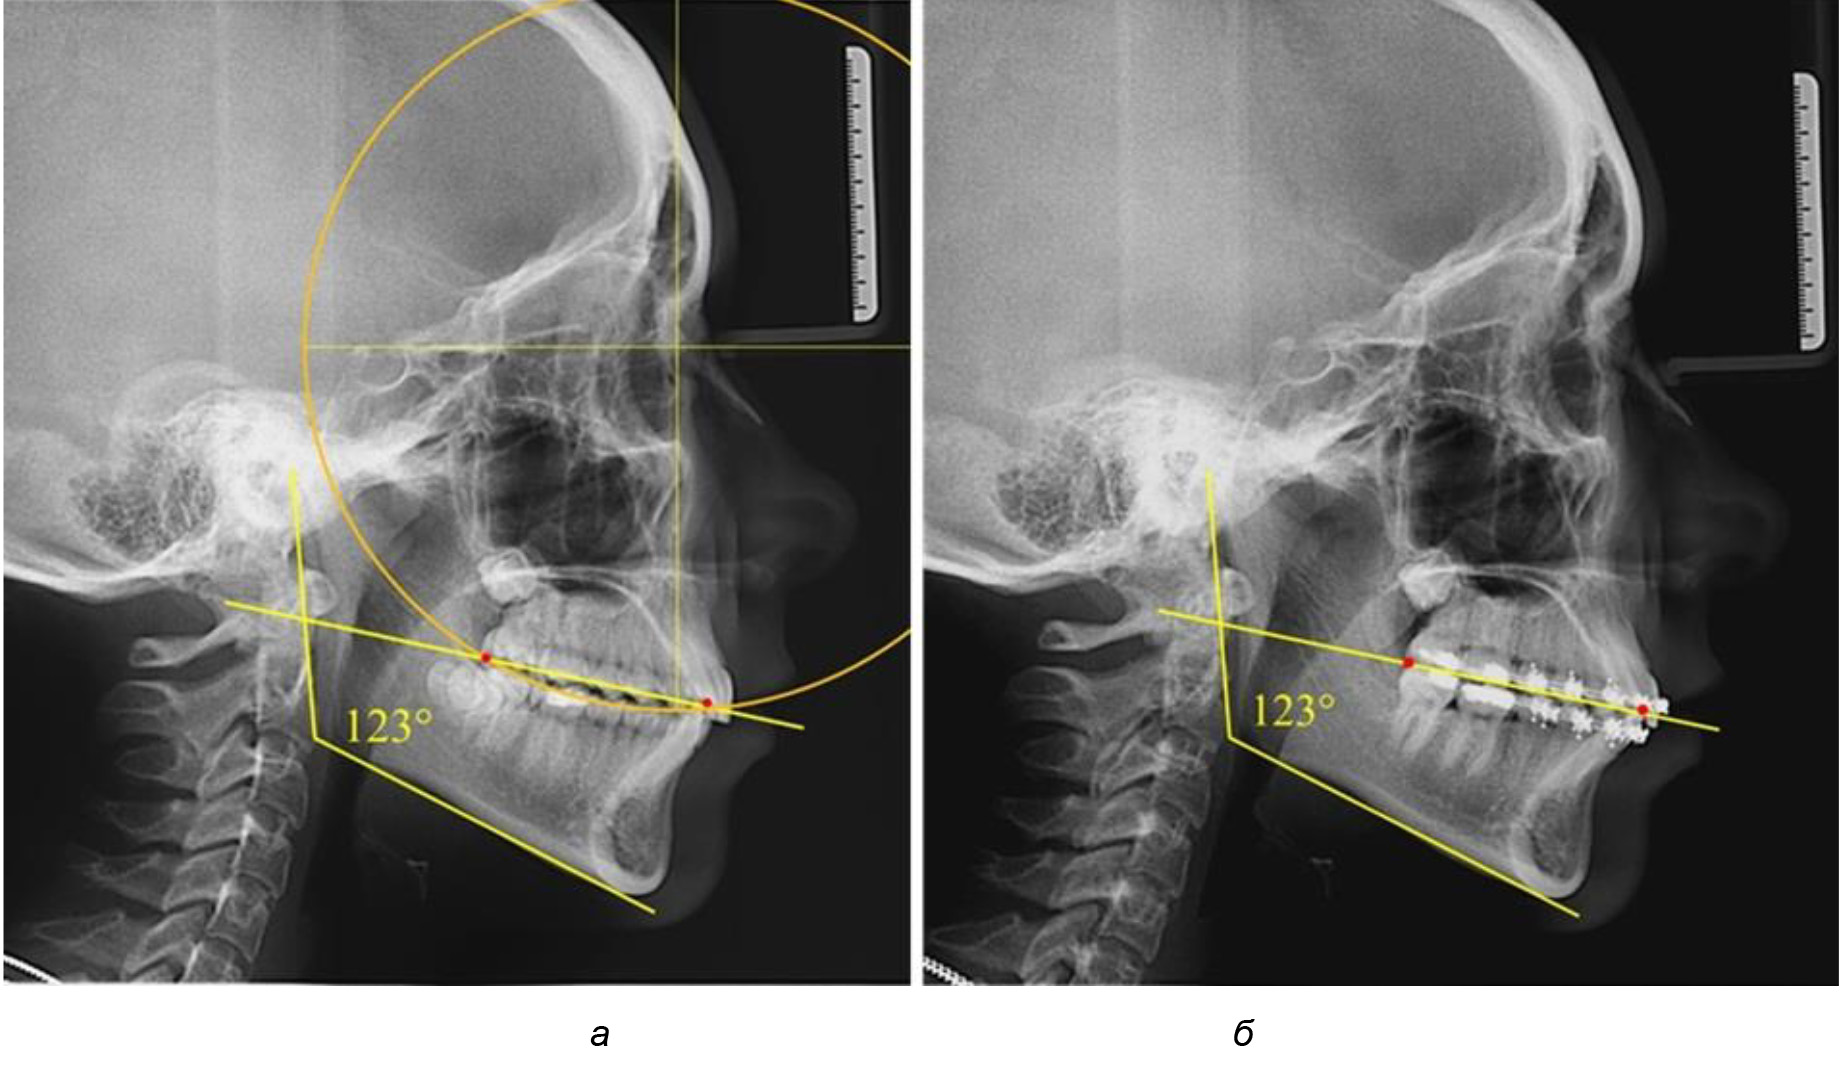

Деление величины радиуса круга к длине окклюзионной линии составило 1,623 ± 0,02. Таким образом, для определения радиуса окружности, соответствующей кривизне окклюзионного контура боковой ТРГ, необходимо измерить расстояние между передней и задней окклюзионными точками и последующим умножением полученной величины на число Фибоначчи (рис. 2).

Рис. 2. Особенности кривой Spee на ТРГ (а) и ОПТГ (б) у людей с признаками вертикального роста